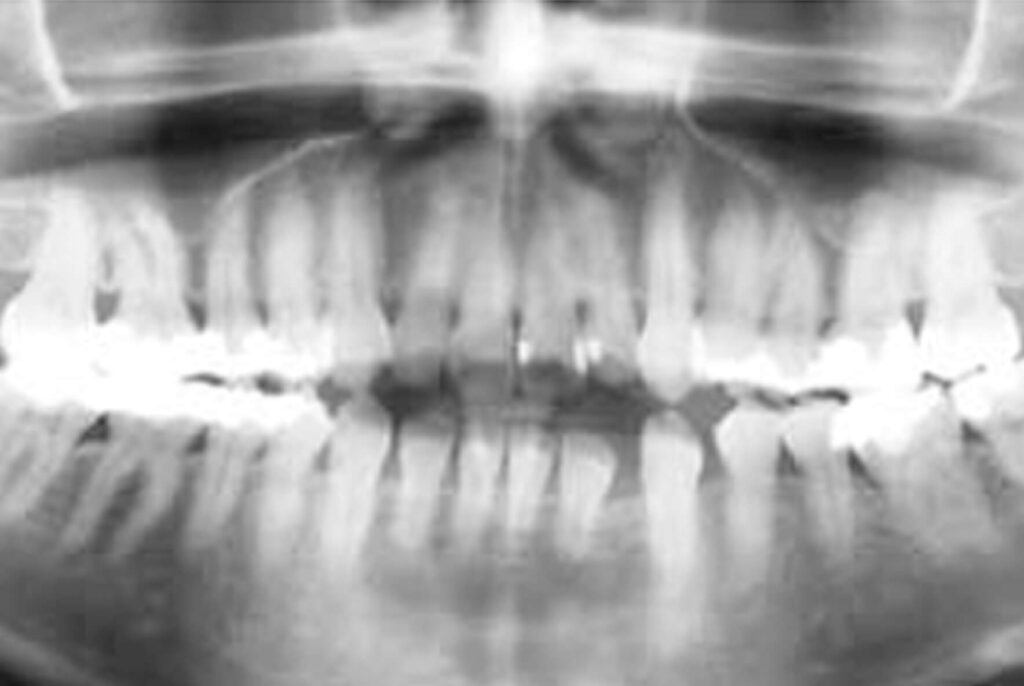

Nas radiografias realizadas ao início do tratamento foi observada a presença de diastemas no hemiarco inferior esquerdo, originados pela ausência do primeiro molar (36). Pode-se notar ainda a ausência do dentes 18 (terceiro molar superior direito), 28 (terceiro molar superior esquerdo) e 48 (terceiro molar inferior direito), cujo a paciente relatou que havia sido realizada as extrações devidas. Não foi notada nenhuma alteração significante nas estruturas adjacentes aos

dentes (Figuras 3 e 4).